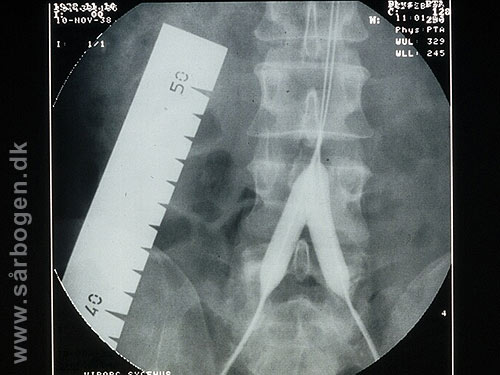

Zoom

Under PTA af iliacak...

Efter PTA af iliacak...